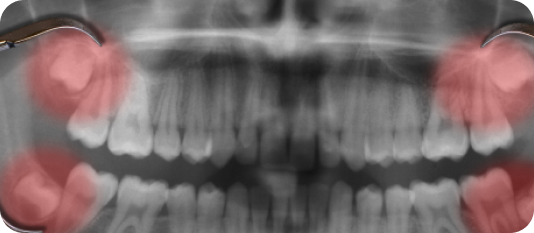

Gums can be treated for diseases leading to tissue infection, bone loss and loose teeth leading to gum disease that can occur when you do not take proper care of your oral health.

Using digital, advanced software, our dental experts will come up with a scientific The surgery can help treat the infected part of the gums by extracting the bacterial formation from under the tissue and sewing it back. This slowly reduces inflammation and prevents further gum disease, improving overall gum health and aesthetics of your facial structure.plan by predicting the result by analysing the tooth movements and deducing the invisible aligners before and after positions.

Take control of your gum health with advanced treatments! Gum surgeries offer effective solutions for gum problems that may not be resolved through non-surgical methods. From gum grafting to periodontal flap surgery, our skilled team will restore your gum health and help you achieve a healthier, more confident smile.